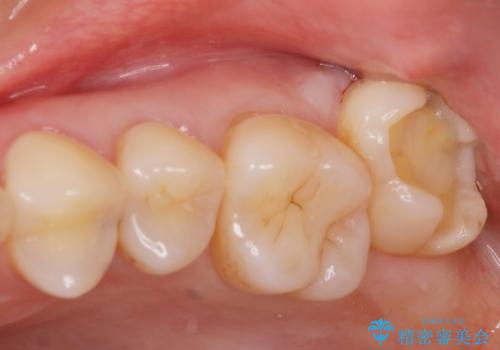

奥歯の黒いのが気になる。

- 奥歯が黒いとの事で来院。

歯の表面がう蝕になっていたので拡大鏡でう蝕を除去し、e-maxインレー(セラミックインレー)で治療を行いました。

適合の良い詰め物が入りました。

セラミックスは劣化しないので虫歯の再発のリスクが低くなります。